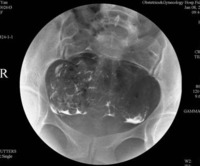

7、在透视下缓慢注入造影剂至宫腔和/或输卵管显示满意后摄片;

1、能清晰显示子宫腔和/或输卵管轮廓、形态。

2、对比度满意。